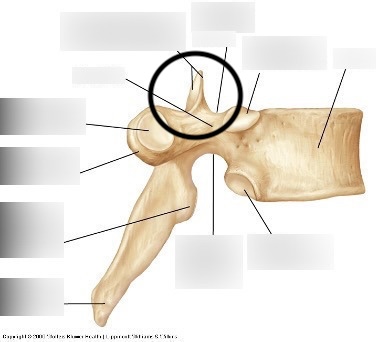

vertebral foramen

knowt flashcard image

transverse processes - vertebra

spinous process

superior articular processes

inferior articular processes

costal facets